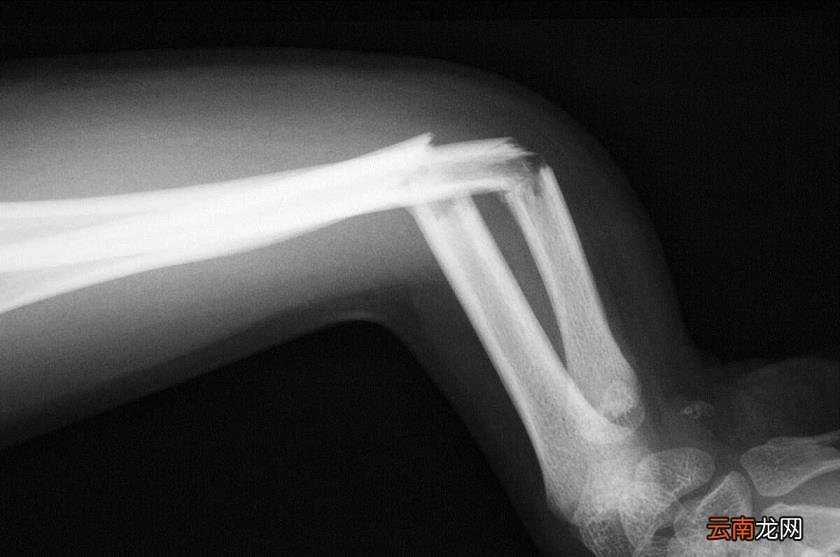

文章插图

我们的骨头中活跃着多种“活细胞”,例如骨原细胞、成骨细胞、骨细胞等等,其中骨原细胞能够改建或修复骨组织,如果骨头裂了或者断了,完全可以再生长 。

这一特点也使人类区别于无脊椎动物,像蜗牛这类动物,万一外壳破碎了,只能是死路一条了 。